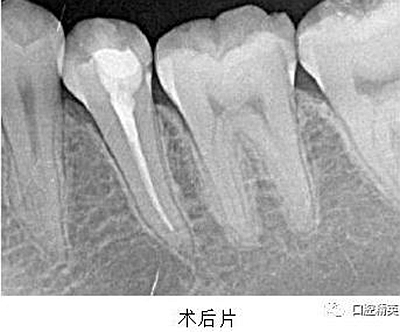

處置:經(jīng)患者及家屬知情同意后,35 局麻,放置橡皮障,去腐,開髓,可見黑色感染物流出,定位根管口,建立直線通路,10# K 銼疏通根管,確定工作長度(19mm),機用鎳鈦器械(M3),次氯酸鈉全程浸泡沖洗,預(yù)備根管至 35 號,0.04 錐度,2ml EDTA 沖洗液緩慢勻速沖洗,超聲蕩洗。試主尖 X-ray 可見恰充,吸潮紙尖拭干根管,導(dǎo)AH-Plus 糊劑,連續(xù)波熱牙膠垂直加壓充填,術(shù)后 X-ray可見根管恰充,SDR 封閉根管口,復(fù)合樹脂充填窩洞,恢復(fù)牙齒形態(tài),調(diào)牙合,拋光。醫(yī)囑

2、扁平根管充填時,應(yīng)該采用混合技術(shù)。因為主牙膠尖往往不適合扁平根管的形態(tài),使得攜熱器很容易將主牙膠尖全部帶出根管。混合技術(shù)是將連續(xù)波熱牙膠垂直加壓充填法和側(cè)方加壓充填法混合使用,即在插入主尖之后,使用側(cè)方加壓器加壓,追加數(shù)根副尖,直至根尖區(qū)充填致密,繼而使用攜熱器切斷,垂直加壓,熱牙膠回填。

3、根管充填完成之后,要使用流動樹脂或者 SDR 嚴(yán)密封閉根管口,酌情墊底,優(yōu)化洞型,之后再行樹脂充填或嵌體等的修復(fù)。本例建議行嵌體修復(fù),患者由于個人時間問題,希望暫緩修復(fù),于是采用樹脂充填修復(fù)術(shù)。